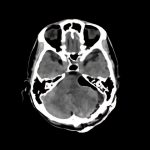

症例 '15年6月

No.

年_番号

手術年月

患者年齢

’15_85

'15年6月

50代

病名

術式

備考

聴神経鞘腫

断層撮影

手術前

1

手術前2

手術後